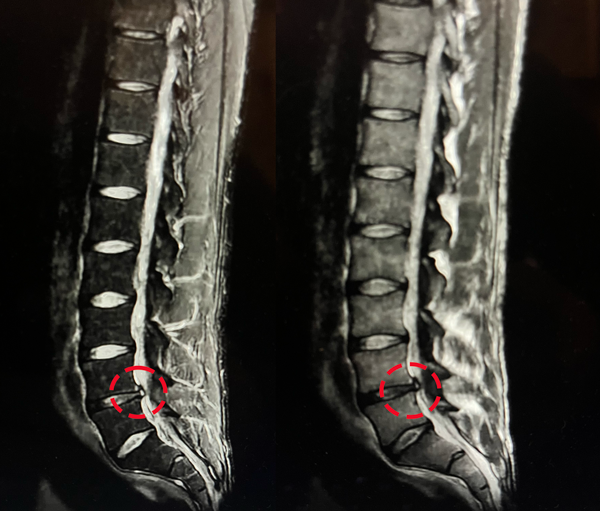

Mi hernia discal L4L5

Desde que tenía 20 años, tuve multiples episodios de lumbago agudo. El lumbago agudo es un dolor repentino en la parte baja de la espalda que te impide moverte.

La última vez que me quede con la espalda bloqueada termine en el suelo sin poder moverme.

Dos meses después ya estaba de vuelta al gimnasio, entrenando al 95% de mis capacidades.

Pero fruto de una leve escoliosis y una hernia discal me bloqueé la espalda varias veces hasta experimentar una ciática. Así, tuve que aprender a recuperarme de mis lesiones y volver a vivir sin dolor. Hoy puedo entrenar 5 veces a la semana sin ningún riesgo.